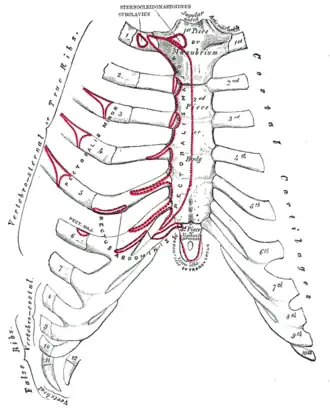

Superfície anterior do esterno e cartilagens costais.

Superfície anterior do esterno e cartilagens costais. -